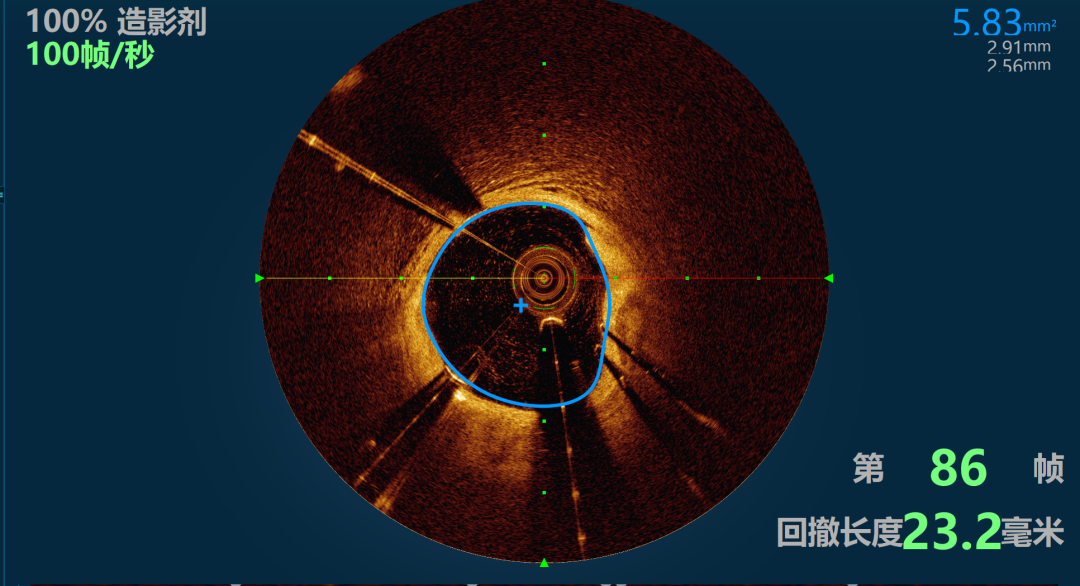

行前降支OCT检查

图3-4

郝六一主任查看Optimiro图像,对原来支架复查,支架内轻微软斑块增生无需处理,由于前降支中段最小管腔面积1.47mm,斑块符合70%以上,斑块性质纤维钙化斑块,钙化成度在180度左右 有PCI指征, 术前郝六一教授指出这就是腔内影像检查带来的好处,由于OCT可以精准计算出斑块负荷和残余管腔面积,在临界病变中更加精准的给出指导数据。